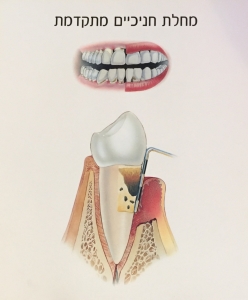

פריודונטיטיס – השלב שבו ישנה התפתחות של הדלקת לכרונית ותגובת נגד של המערכת החיסונית כנגד רכיבי הגוף עצמו.

כתוצאה מכך נגרם הרס נרחב של החניכיים ושל רקמת העצם התומכת בשן במקרה של פגיעה בעצם המצב אינו הפיך אך ניתן לעצירה בטיפול מתאים ובשמירה על היגיינה תקינה כך שהמצב לא יחמיר.

קצב התהליך הדלקתי שונה מאדם לאדם ותלוי רבות בהרגלי ההיגיינה של כל אחד ואחד.